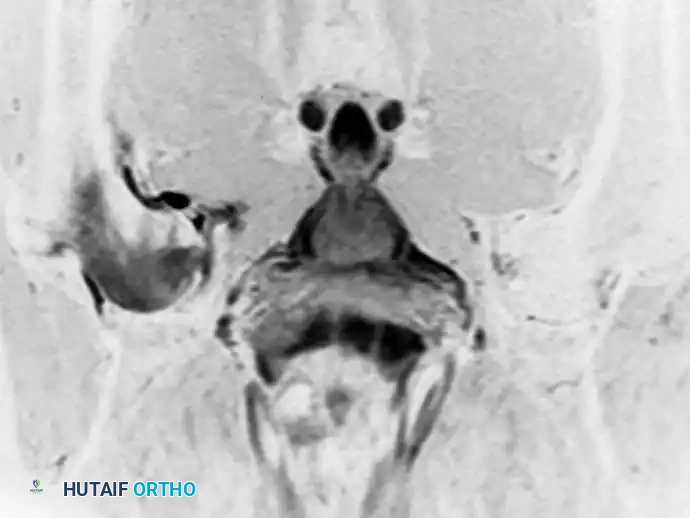

لا تقتصر قوة الرنين المغناطيسي على مفصل الورك فحسب، بل تمتد لتشمل المفاصل الأخرى كالركبة، مما يثبت فعالية هذه التقنية في كشف أدق التفاصيل التشريحية والمرضية في العظام والغضاريف. نستعرض هنا بعض الأمثلة التي توضح دقة الرنين المغناطيسي في تشخيص إصابات المفاصل:

هذه الصور تؤكد بما لا يدع مجالا للشك أن الاعتماد على الرنين المغناطيسي يوفر خريطة طريق واضحة للطبيب المعالج، سواء كان يتعامل مع كيس زلالي، أو كدمة عظمية، أو كسر خفي في صفيحة النمو، أو آفة غضروفية، مما ينعكس إيجابا على دقة التشخيص في مفصل الورك والمفاصل الأخرى.